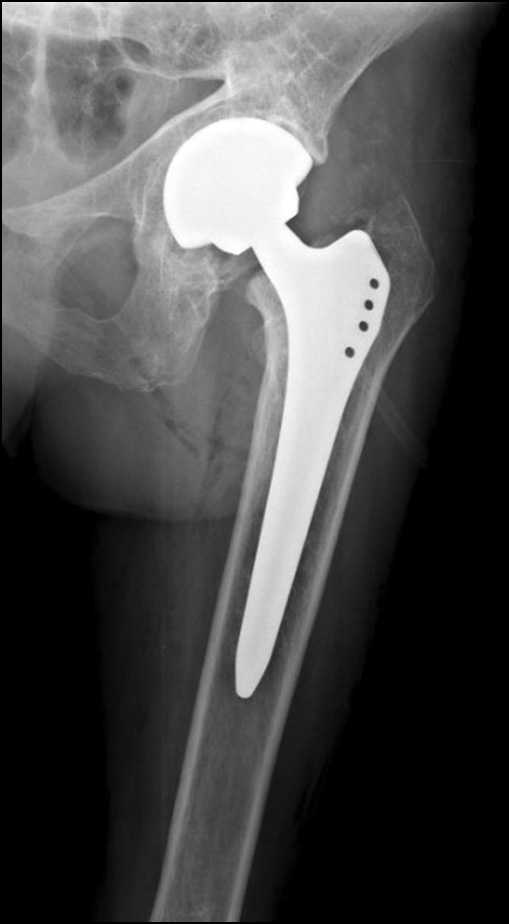

При современном обеспечении ЗФТ использование бесцементных имплантатов показало большую долговечность в сравнении с цементной фиксацией. Это объясняется тем, что при БГ сохраняется репаративный потенциал костной ткани, что обеспечивает остеоинтеграцию и вторичную биологическую фиксацию бесцементных эндопротезов [16]. При колбовидном расширении проксимального отдела диафиза бедра мы отмечали проксимальную фиксацию компонентов в межвертельной зоне (рис. 6). Хорошие результаты применения укороченных бедренных компонентов также подтверждают это (рис. 7).

Рис. 6. Проксимальная фиксация бедренного компонента типа Zweymüller при расширении канала бедренной кости у пациентки с болезнью Гоше.

Fig. 6. Proximal fixation using a Zweimüller-type femoral component in a patient with Gaucher disease and widened femoral canal.